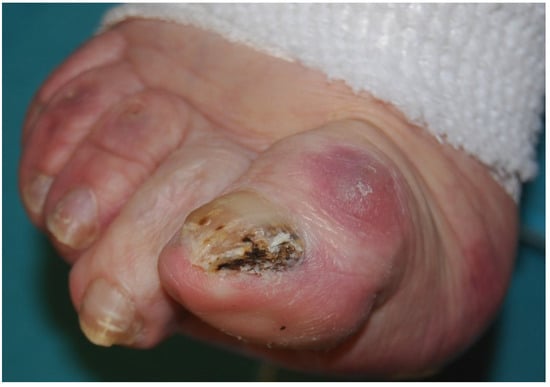

Fungi reach the nail through the hyponychium and invade the undersurface of the nail unit plate spreading proximally. Distal and lateral subungual onychomycosis (DLSO) usually affects one or both of the great toenails and is also usually associated with tinea pedis [7]. The nail plate appears yellow-white, is detached due to onycholysis, with distal subungual hyperkeratosis (Figure 1). Less frequently, a brown, black or orange discoloration of the onycholytic nail can be seen (Figure 2). A possible presentation of DLSO due to dermatophytes is dermatophytoma, a subungual accumulation of hyphae and scales, scarcely reached by antifungals, which require excision of the area and systemic treatment. DLSO may be associated with black pigmentation of the nail (“fungal melanonychia”) (Figure 3), when the pathogen is the Melanoides variant of Trichophyton rubrum or other fungi that produce melanin, like Neoscytalidium dimidiatum or Aspergillus niger [11]. Onychomycosis due to non-dermatophytes is typically associated with a marked periungual inflammation (Figure 4). Differential diagnoses of DLSO include traumatic onycholysis (usually symmetrical and subungual hyperkeratosis is absent) and nail psoriasis (diffuse hyperkeratosis, several/all toenail involved, others skin and nail signs of psoriasis).

Figure 4. Onychomycosis due to molds, presenting the typical periungual inflammation.